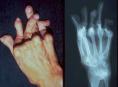

Artritis reumatoideaDistintos virus de herpes se asocian con la artritis reumatoide (AR), según un estudio desarrollado en el Hospital Clínico San Carlos de Madrid, aunque los autores señalan que no están seguros de sí estos virus juegan un papel causal en la patología.

En este trabajo, que publica el número de septiembre de “Annals of Rheumatic Diseases”, evaluaron los niveles de varios herpesvirus en células nucleares de sangre periférica (CMSP) y en muestras séricas de 60 pacientes con artritis reumatoide y de 75 controles sanos.

El análisis de las muestras de CMSP reveló que el virus de Epstein-Barr era mucho más común en los pacientes que en los controles, al igual que el herpesvirus humano 6. Los autores sugieren que quizás fuera útil la monitorización del ADN de herpesvirus en pacientes con AR para ver si los incrementos de la carga viral correlacionan con exacerbaciones de la patología.

Señalan asimismo que hace tiempo que se sospecha que las infecciones virales pueden jugar un papel en el desarrollo de AR. Podría ser que la peor inmunidad celular de estos pacientes conduzca a niveles más elevados de estos virus que en sujetos sanos, o que la propia patología haga a los pacientes más proclives a la infección o la reactivación con estos virus.